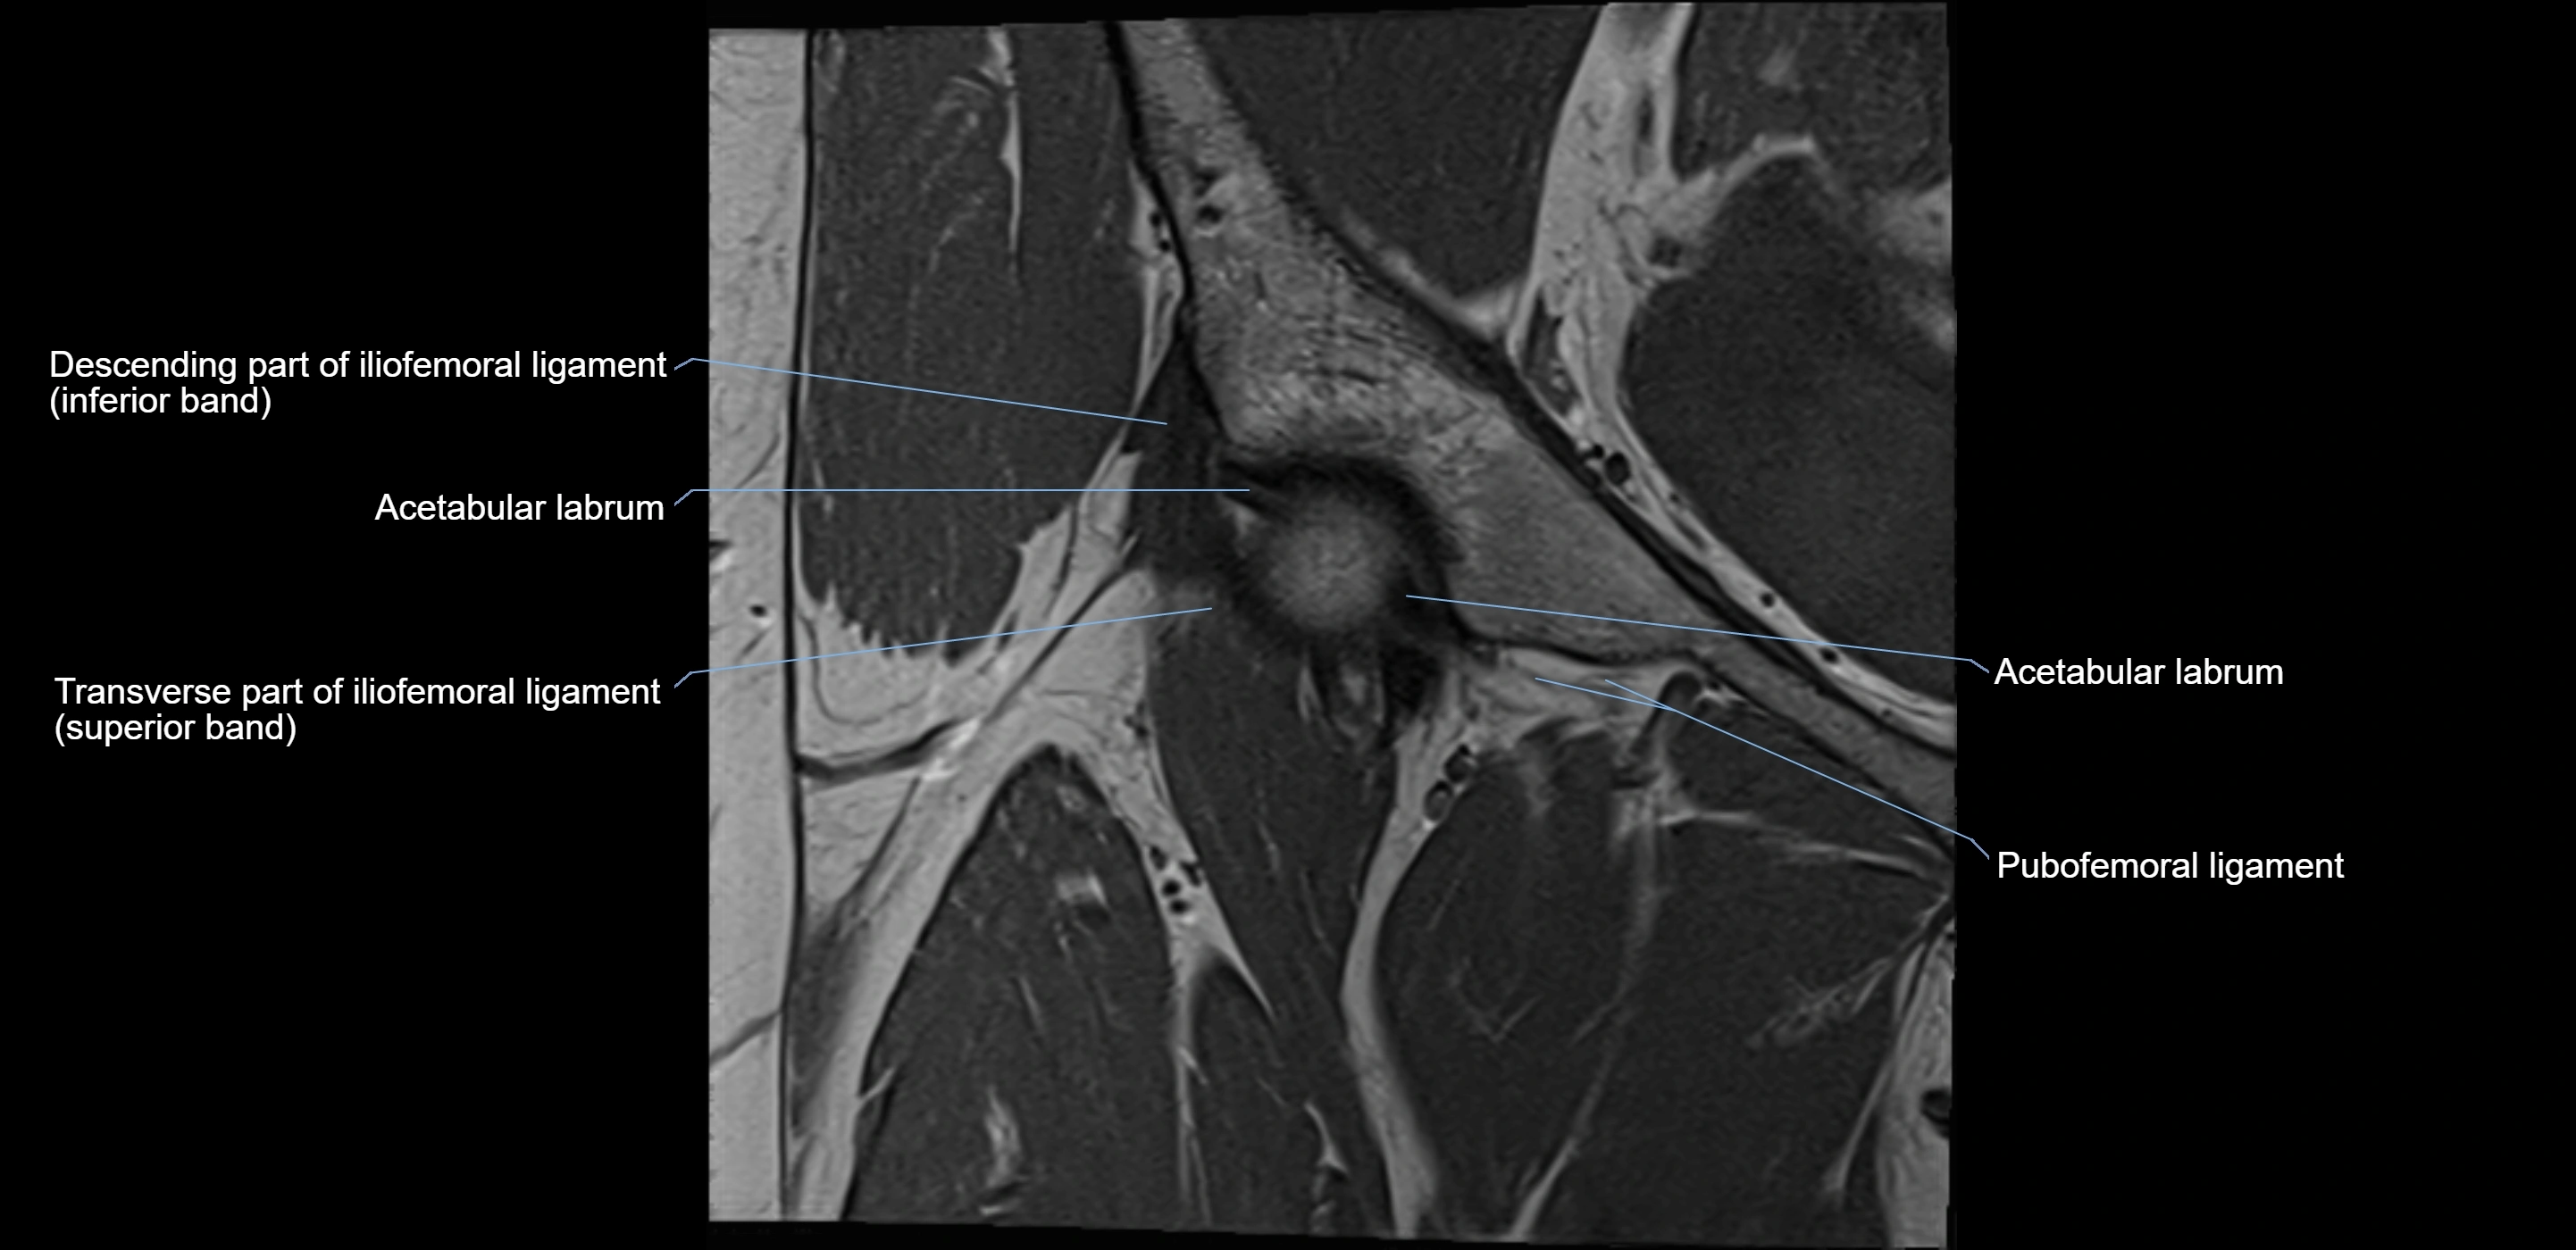

The acetabular labrum is a fibrocartilaginous ring that surrounds the rim of the acetabulum in the hip joint. It deepens the hip socket, increases joint stability, and maintains a suction seal that preserves negative intra-articular pressure. Structurally, the labrum transitions from hyaline cartilage of the acetabulum to dense fibrocartilage at its free edge.

It is triangular in cross-section, with its base attached to the acetabular rim and its apex projecting toward the femoral head. The labrum is most robust superiorly and anteriorly, where load bearing is greatest, and relatively thinner inferiorly.

Structure and Relations

• Superior and anterior labrum: thickest portions, stabilizing against anterior dislocation

• Inferior labrum: blends with the transverse acetabular ligament bridging the acetabular notch

MRI Appearance

T1-weighted images:

• Labrum: low signal intensity (dark)

• Surrounded by intermediate signal joint fluid (bright on arthrogram)

• Tears: linear or focal areas of intermediate-to-high signal interrupting labral continuity

T2-weighted images:

• Joint fluid: bright, making labral tears visible as fluid extending into or around labrum

• Degeneration: may show areas of increased signal within labrum